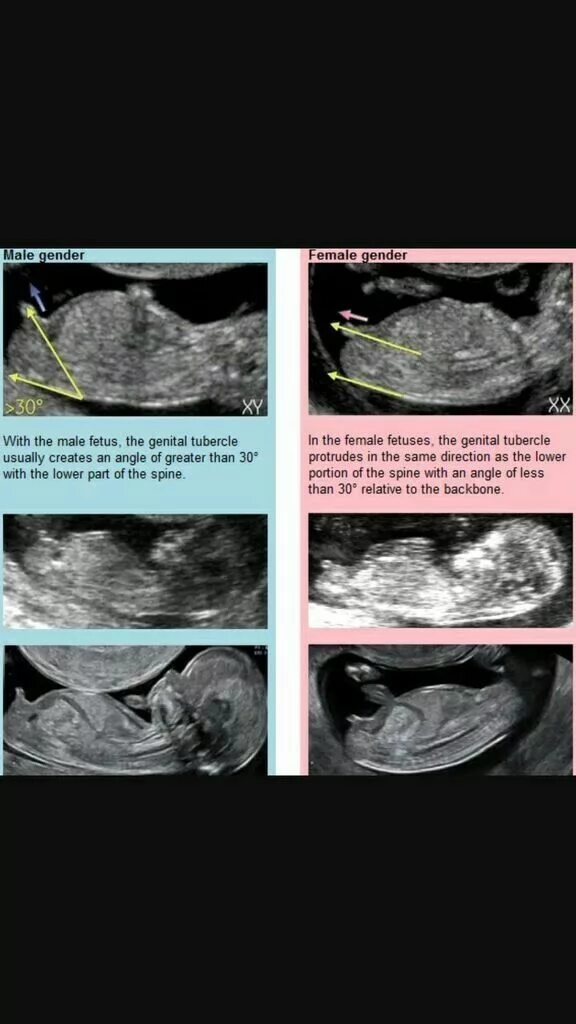

Как определить пол на 20 неделе